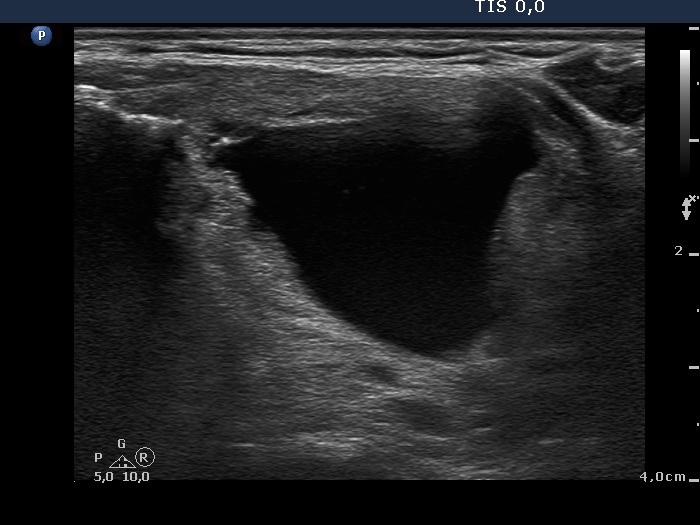

Intranodular hyperechogenic figures - case 608 (ultrasonographic picture 4)

Isthmus, transverse view. This is the cystic part of the lesion.